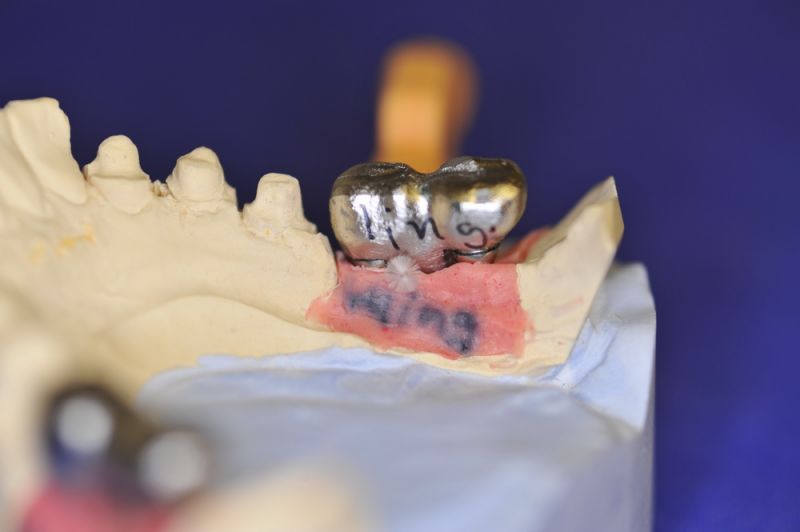

Nun stellte sich heraus, dass der Abstand zwischen den Implantaten sehr gering war, weil die Einschubrichtungen der Aufbauten sich zum Teil gegenseitig im Wege standen. Konfektionierte Teile mussten individuell umgeschliffen werden, dabei das Ziel, den Biss korrekt einzustellen nicht aus dem Auge zu verlieren.

Heute war nun Gerüsteinprobe, mit all den Problemen der Umsetzung zwischen Laborsituation und Mundsituation. Siehe Stichpunkt "Schnittstellenproblematik"! was bei Zähnen, auf Grund deren Eigenbeweglichkeit im Kieferkochen kein Problem wäre, ist bei drei unbeweglichen Implantaten ein Riesenproblem. Darüber spricht nur in aller Regel Niemand! Es musste viel fein nachgearbeitet werden.

4 Stunden haben wir heute Temporäre Aufbauten und provisorische Kronen entfernt. Definitive Aufbauten im Munde eingeschraubt. Eine erneute Bissregistrierung durchgeführt und die Arbeit neu artikuliert. Neue Provisorien mussten auch wieder hergestellt werden.